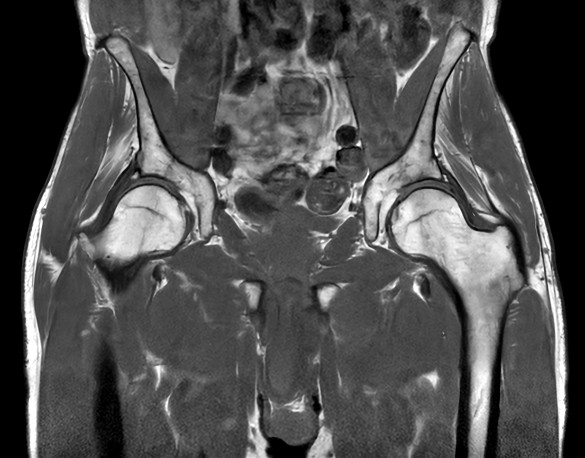

Fast bilateral hips, with SmartSpeed Precise

Fast bilateral hips_MR 5300_R11